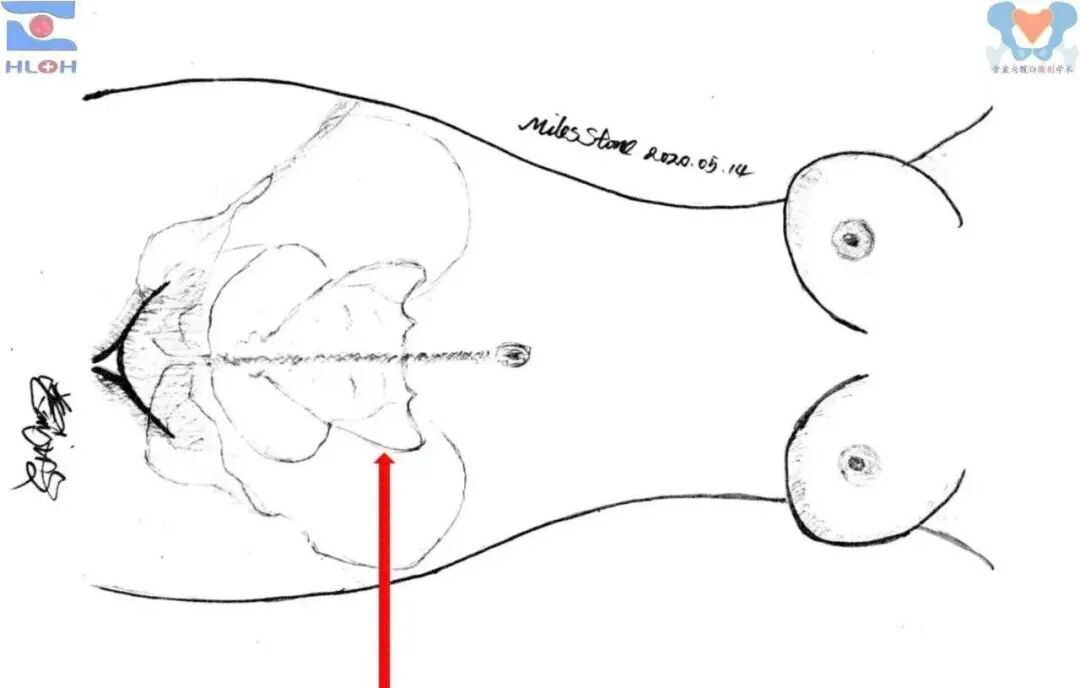

针对这一痼疾,我们有着支点之心的创伤骨科医者,只要遵循事实、发现规律并稍做变通就可以迎刃而解之。在术前骨盆轴向CT断层图像上,我们规划骶髂螺钉置入的过程中发现两个基本事实,一是骶髂螺钉完全位于骨盆横断面内,二是除了进钉点之外,唯一能限制骶髂螺钉位置的参数就是螺钉与骨盆冠状面(双侧髂后上棘的连线)的夹角。

骨盆轴向断层CT图像上骶髂螺钉置入的规划

因此,在标准骶骨侧位像上建好进针点后,我们只要把导针调整在骨盆的横断面内,并进一步地将术前所测量的冠状面夹角复制出来,轻浅置入导针,转透骨盆出入口位像,我们会发现其指向已然良好而无需再做任何调整操作,仅需引导导针就位即可,从而大大地简化了骶髂螺钉置入手术并确保了手术的安全性和精准性。